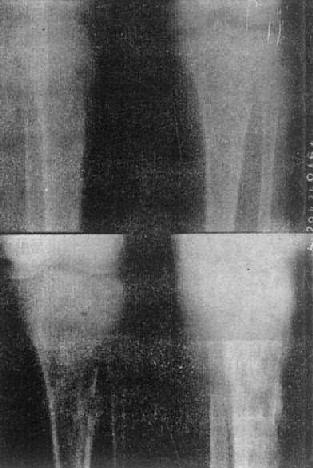

死骨的X线表现是骨质局限性密度增高(图2-1-13),其原因:一是死骨骨小梁表面有新骨形成,骨小梁增粗,骨髓内亦有新骨形成即绝对密度增高。二是死骨周围骨质被吸收,或在肉芽、脓液包绕衬托下,死骨亦显示为相对高密度。死骨的形态因疾病的发展阶段而不同,随时间而渐被吸收。恶性骨肿瘤内的残留骨有时为死骨,有时为活骨。

图2-1-13 胫骨慢性化脓性骨髓炎

上图可见骨破坏及骨膜反应,有死骨形成。下图为半年后,死骨更为明显

骨质坏死多见于慢性化脓性骨髓炎,也见于骨缺血性死和外伤骨折后。